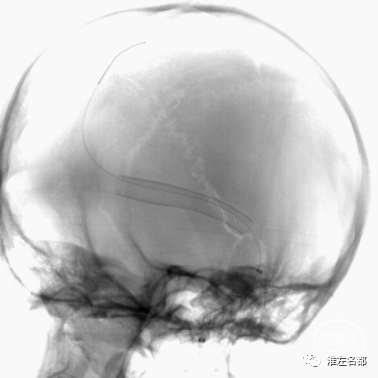

术后第2日,颅脑CTV:右侧横窦内支架展开形态良好(红箭),管腔通畅。

术后第2日,复查CTV示:双侧横窦内支架展开形态良好(红箭),管腔通畅。